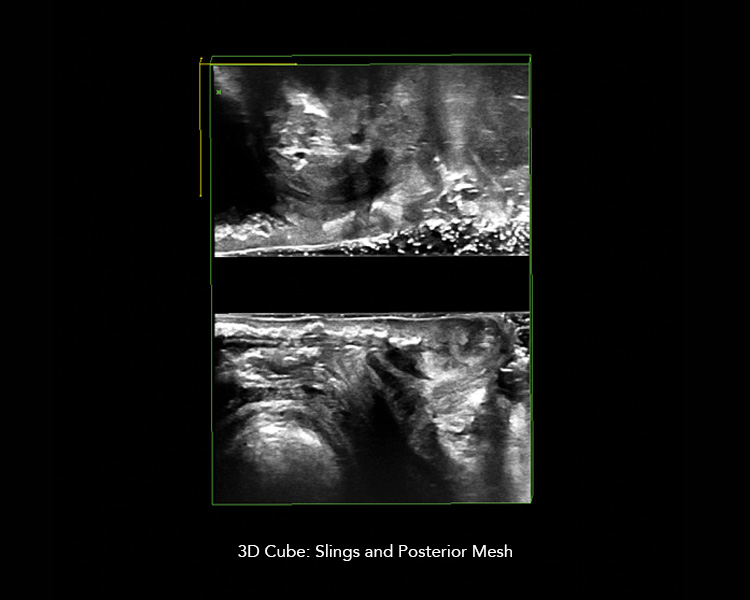

Multicompartment imaging using transperineal, endovaginal, and endoanal scanning enables you to get the information you need for the full pelvic floor picture. 3D imaging allows you review the 3D dataset after the patient’s visit.

• Tapes and meshes

Easily manipulate 3D datasets

• Manipulate 3D datasets to see detailed structures from any angle you choose

• Angle and cut planes intuitively

• Compare 3D datasets by having several datasets open simultaneously